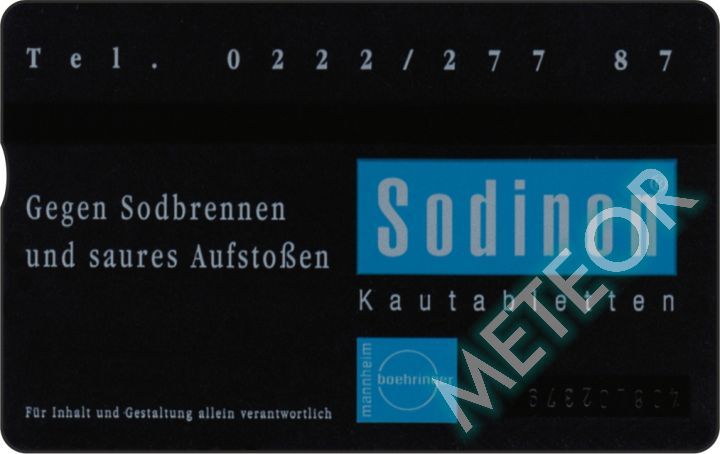

Meteor-Code: TKA P358

ANK-Nummer: P 358

Herausgeber: Telekom Austria

Auflage: 1.000

Seriennummer: 408L 02000 - 02999

Schlagworte: Pharmazie